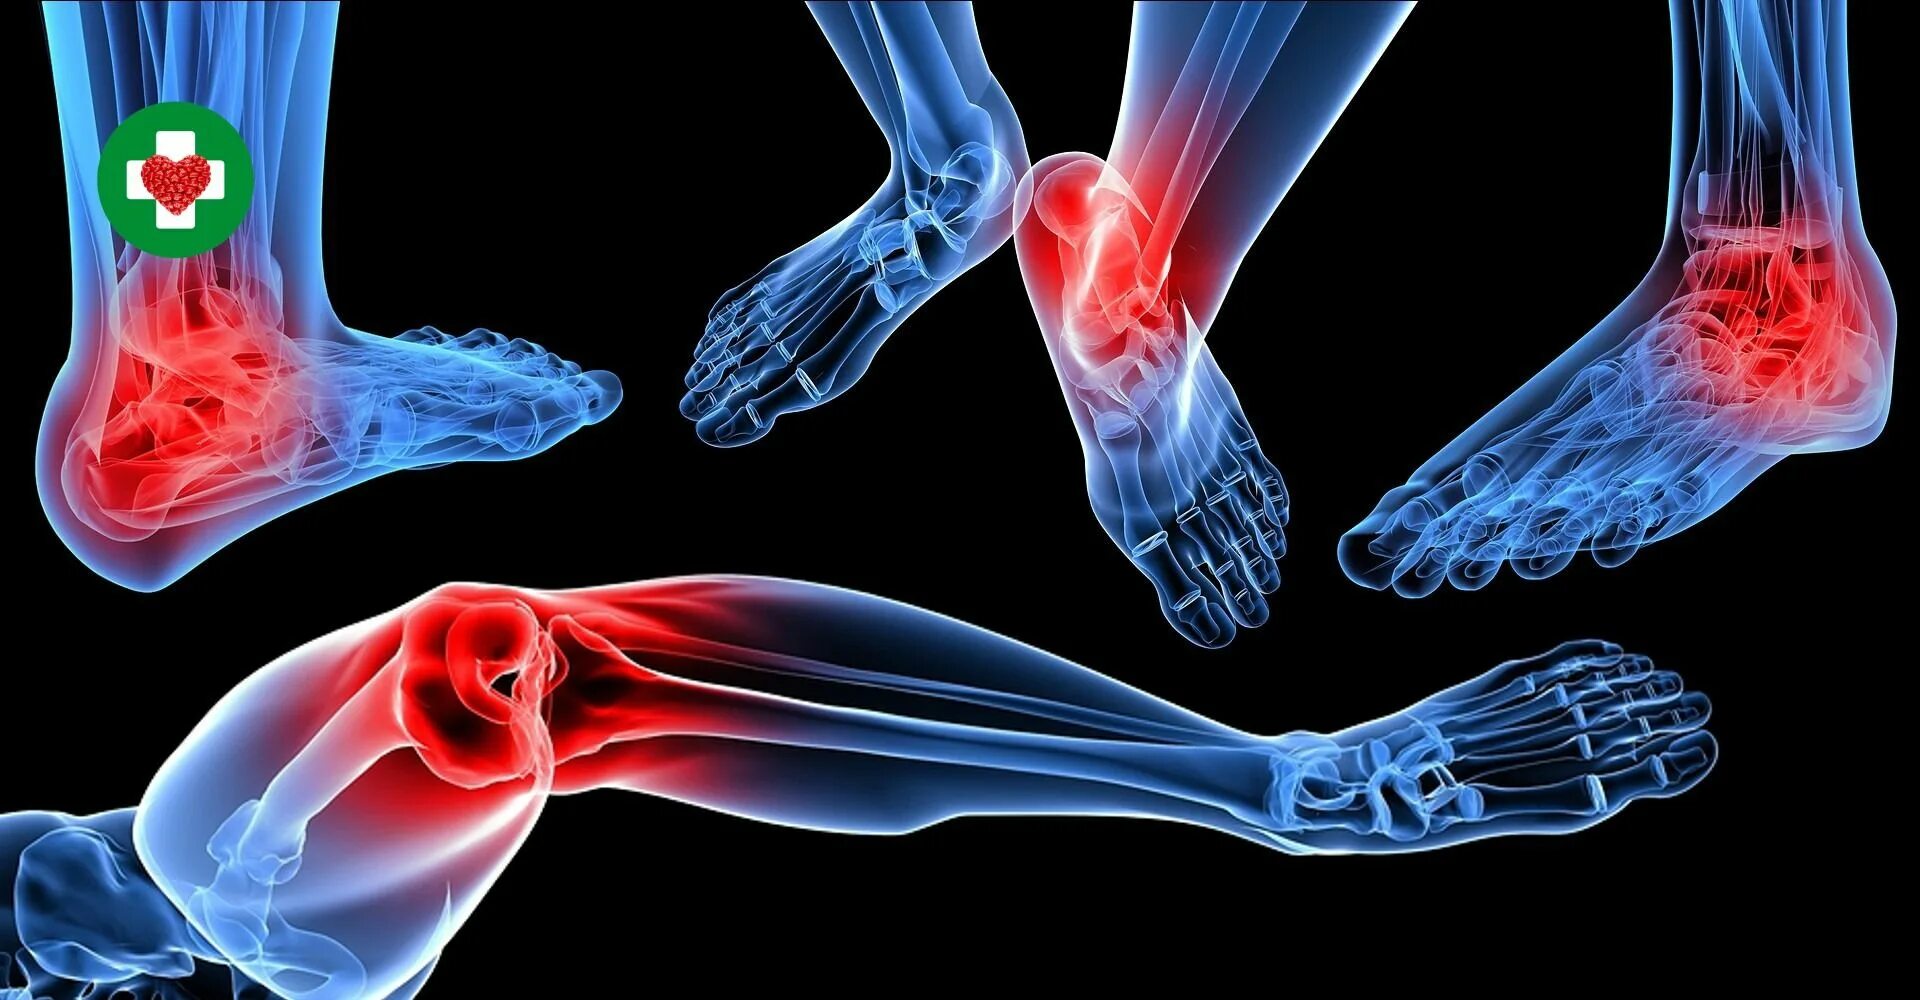

Ревматизм ног